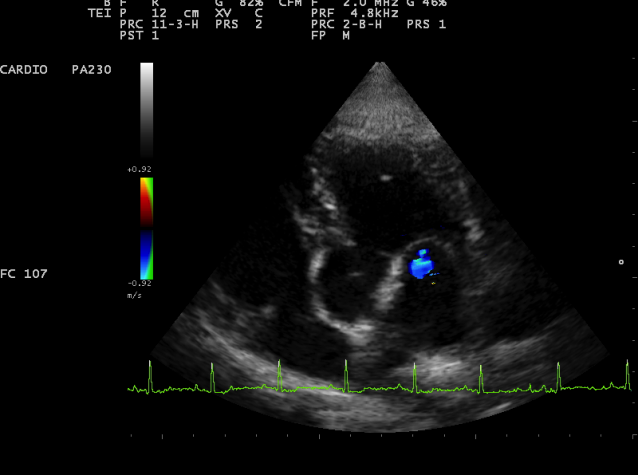

Échographie cardiaque chien & chat